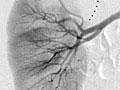

Durante una angiografía, el médico le introducirá un tubo delgado y flexible en un vaso sanguíneo en la ingle o el brazo. Este tubo se llama catéter. El médico guía el tubo hasta el vaso sanguíneo que se va a examinar. A continuación se inyecta un tinte a través del tubo para hacer que la zona sea más fácil de ver. Se toman radiografías o imágenes de la zona.

Una vez que se haya colocado el catéter, se inyecta el material de contraste a través de él. Es posible que se le pida que inhale y contenga la respiración durante varios segundos. Se tomarán varias imágenes radiográficas, una tras otra. Estas estarán listas de inmediato para que su médico pueda observarlas. Debe permanecer muy quieto para que las imágenes sean nítidas. Es posible que se tomen más imágenes.